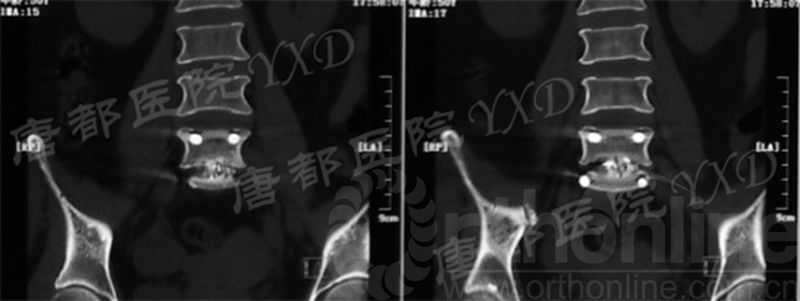

影像学检查:

诊断:腰椎椎间融合术后融合器后移

手术方案:显微镜辅助MI-TLIF腰椎翻修术

术中视频:http://api.orthonline.com.cn/attach/Case3.mp4(术中发现因前次手术全椎板及关节突切除,TLIF的第一步,即关节突关节的定位落脚点难以找到。显微镜下通过Kambin三角解剖位置,进行从外至内的解剖,寻找cage尾端;此外,因大量瘢痕渗血,难以进行充分止血;但在显微镜的照明和放大视野下,操作均可在不伤及神经的前提下进行。由于终板骨质吸收,椎间隙塌陷,导致术野内可同时看到出行根和走行根。而在显微镜下,能够通过调整景深和视线角度,精准充分处理椎间隙骨性终板。无手术并发症)